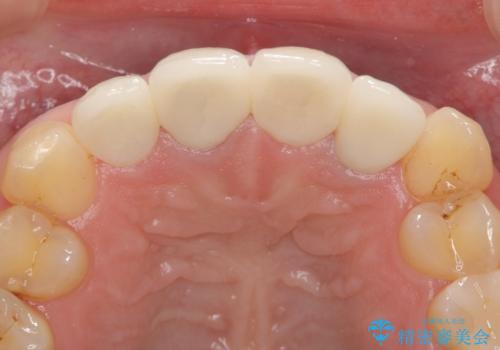

見た目改善のため、前歯4本をオールセラミッククラウン(スペシャル)で補綴しました。

前歯の補綴ではオールセラミッククラウンを希望される患者様が多いですが、オールセラミッククラウンの中でも、エコノミー、スタンダード、スペシャル、エクセレントとランクがあります。

その中でも特に審美性が高いのがスペシャル、エクセレントです。スペシャル、エクセレントは口腔内写真をもとに熟練の技工士が、患者様の口腔内に合わせたオーダーメイドのクラウンを製作致します。